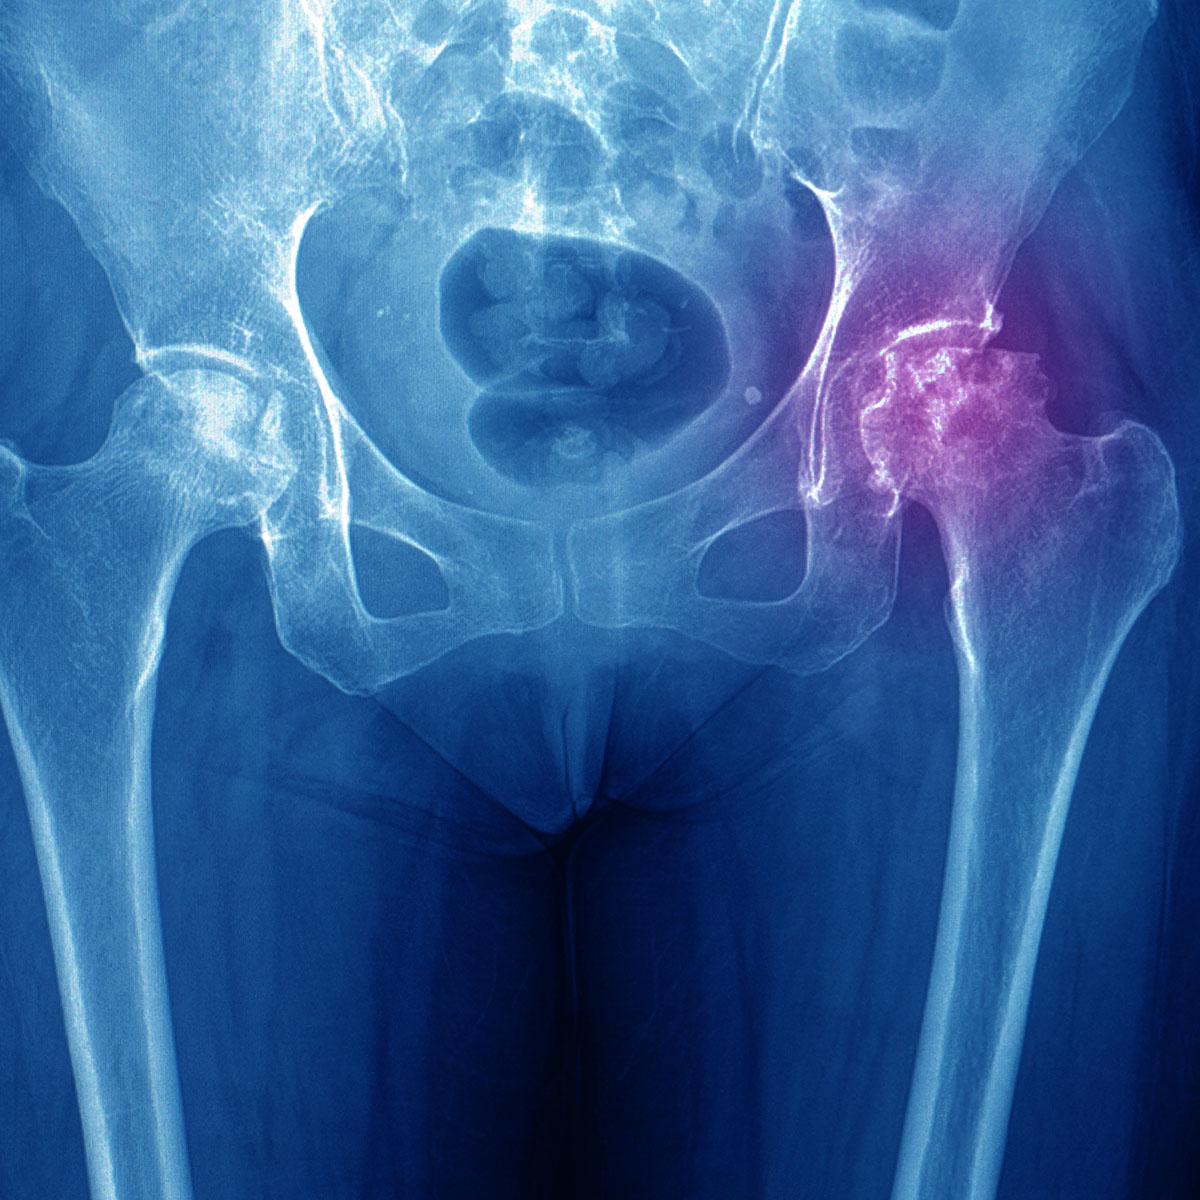

Is Avascular Necrosis Common . avascular necrosis is a disease that results from the temporary or permanent loss of blood supply to the. It typically affects the epiphysis of long bones. avascular necrosis refers to the death of bone tissue that stems from an interruption in its blood supply. it is also known as avascular necrosis, aseptic necrosis, and ischemic bone necrosis. how common is avascular necrosis? The disease most commonly affects the hip joint, and the pain is usually felt in the groin or, less commonly, in the buttock area. in the early stages of avascular necrosis, certain medications may help ease symptoms: Between 10,000 and 20,000 americans develop avascular necrosis.

Avascular Necrosis (AVN) of the Femoral Head Findings on XRay Is Avascular Necrosis Common Between 10,000 and 20,000 americans develop avascular necrosis. in the early stages of avascular necrosis, certain medications may help ease symptoms: It typically affects the epiphysis of long bones. it is also known as avascular necrosis, aseptic necrosis, and ischemic bone necrosis. avascular necrosis is a disease that results from the temporary or permanent loss of blood. Is Avascular Necrosis Common.